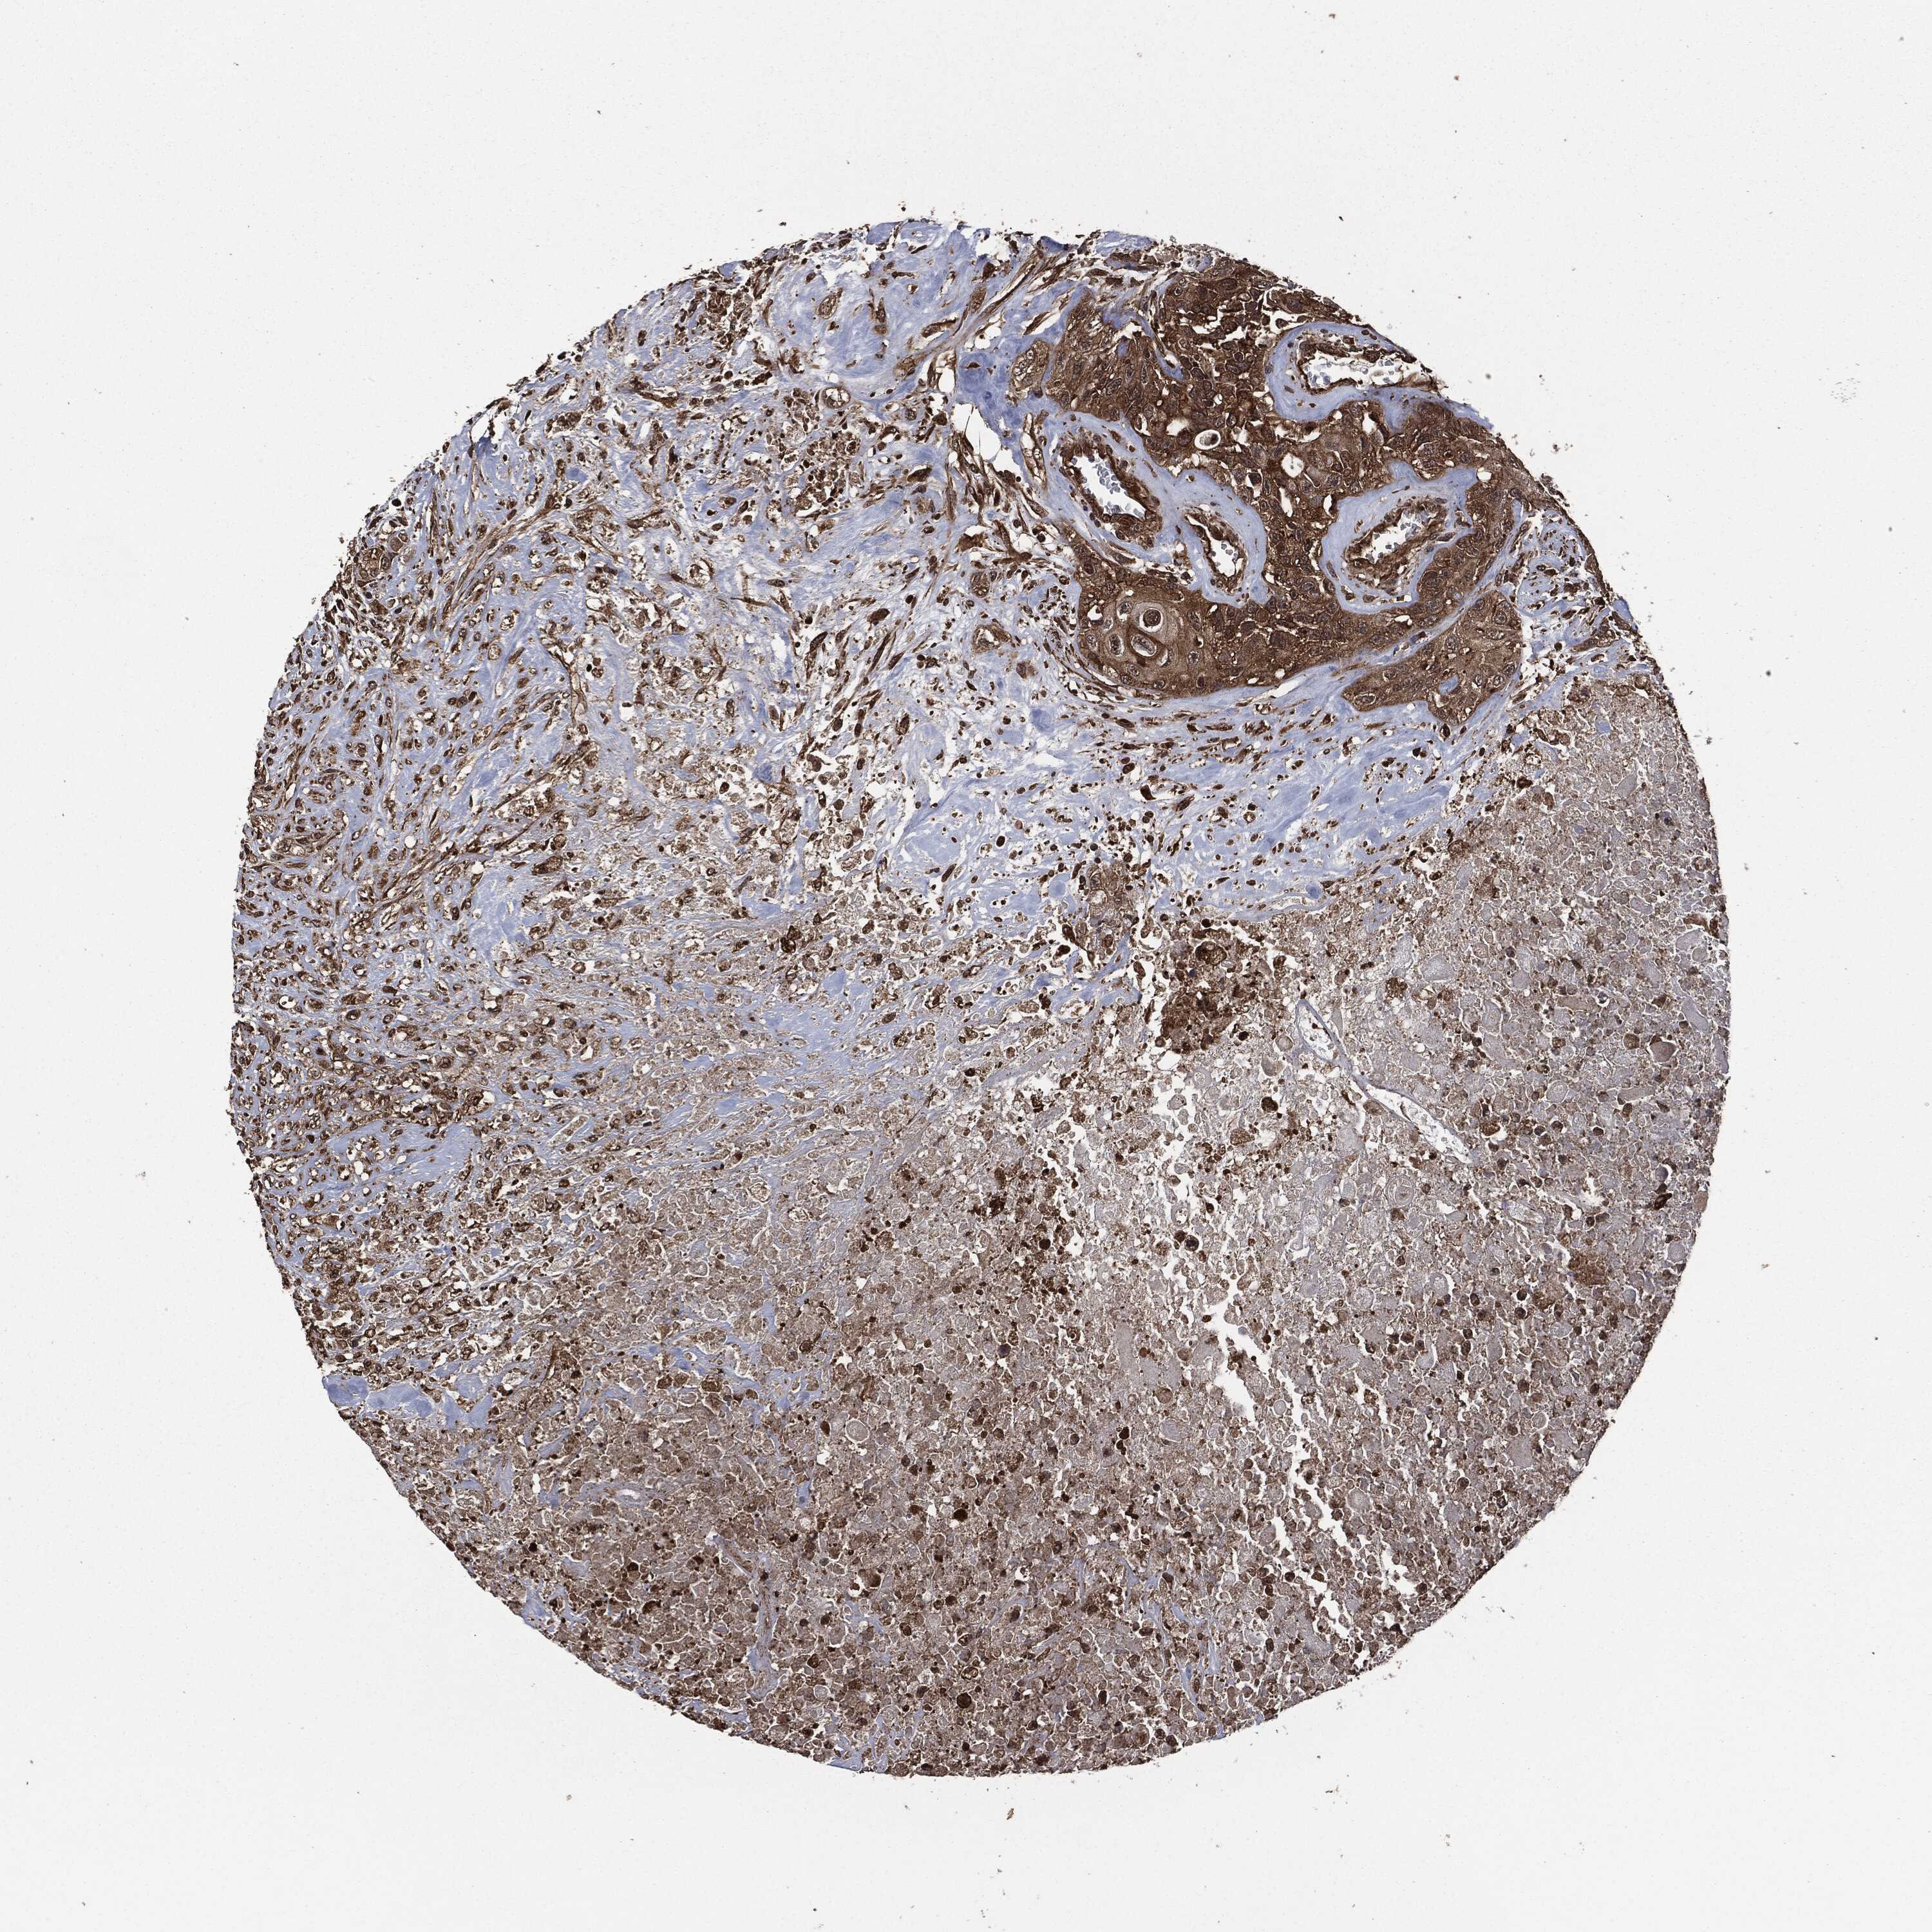

UROTHELIAL CANCER - Protein expressioni

A mouse-over function shows sample information and annotation data. Click on an image to view it in a full screen mode. Samples can be filtered based on level of antibody staining by selecting one or several of the following categories: high, medium, low and not detected. The assay and annotation is described here.

Note that samples used for immunohistochemistry by the Human Protein Atlas do not correspond to samples in the TCGA dataset.

Antibody stainingi

Antibody staining in the annotated cell types in the current human tissue is reported as not detected, low, medium, or high, based on conventional immunohistochemistry profiling in selected tissues. This score is based on the combination of the staining intensity and fraction of stained cells.

Each image is clickable and will lead to virtual microscopy that enables deeper exploration of all samples and also displays staining intensity scores, fraction scores and subcellular localization as well as patient and tissue information for each sample.

HPA049830

Urothelial carcinoma, High grade

Urothelial carcinoma, NOS

Urothelial carcinoma, Low grade

Adenocarcinoma, NOS